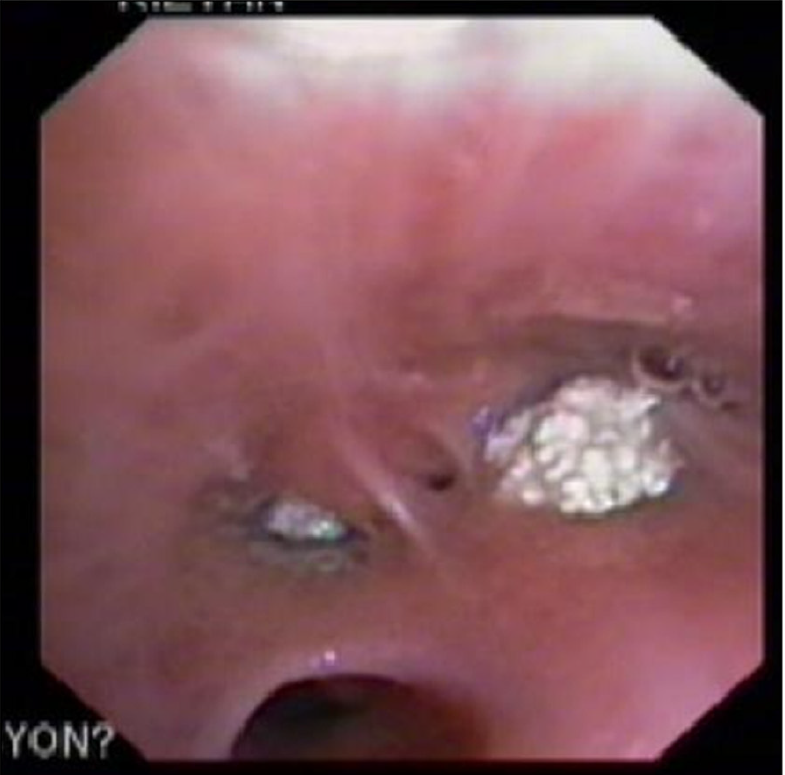

・外科的気道確保がされた翌日、CTが撮影された

気管支狭窄(矢印)と、その周囲の軟部組織腫脹や複数のリンパ節腫脹(矢頭)

T4-6レベルでの気管狭窄が強い